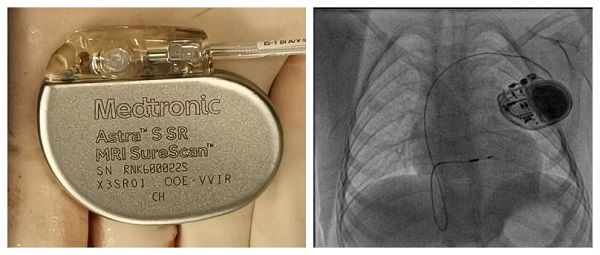

李小梅教授团队为该患儿植入了3.0T MRI长寿命起搏器ASTRA(X3DR01),并实施了目前国际上最为领先的左束支区域起搏治疗,提供了较好的心脏同步性,对术后远期心功能保护具有重要意义。ASTRA(X3DR01)是国内首个实现3.0T&1.5T MRI全身无限制扫描的起搏器,体积为12.25cm3(高42.6mm×宽50.8mm×厚7.4mm),重量仅22.5g,外形小巧。设计上采用全新的电路硬件优化结构及大容量电池,具备超长的使用寿命(预估电池电量17.9年),增加了单次起搏使用周期,对于儿童来说无疑是最好的选择,减轻了多次手术的痛苦。